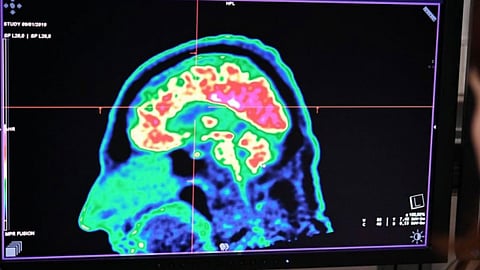

واستخدام خبراء الحاسوب الباحثين في السرطان من معهد أبحاث السرطان ومؤسسة «تراست» الذكاء الاصطناعي للوصول إلى مزيج من العلاج يتكون من «ايفيروليموس» وآخر يسمى «فانديتانيب» لعلاج الورم الدبقي الجسيمي، وهو نوع نادر وسريع الانتشار من أورام المخ لدى الأطفال.

ويعدّ هذا النوع من السرطان وغيره من الأورام الشبيهة صعبة للغاية في الإزالة عن طريق الجراحة للأطفال، بسبب انتشارها الواسع، وغياب حدود واضحة لها تناسب التدخل الجراحي.

لكن بعد تحليل بيانات العقاقير المتاحة، وجد الفريق أن عقار «إيفيروليموس» يمكن أن يعزز قدرة «فانديتانيب» على التسلل عبر الحاجز الدموي للدماغ وعلاج الورم. وثبت فعالية هذا المزيج عند استخدامه لدى الفئران، ويجرى الآن اختباره على الأطفال.